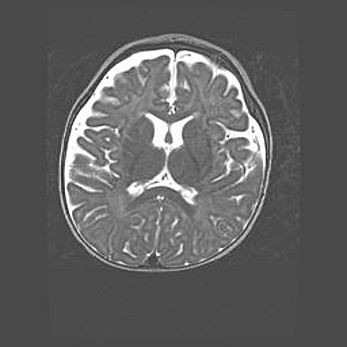

Наружная гидроцефалия с возможной атрофией височных областей.

Возраст: 28 дней

Вес: 3670 г

Пол: мужской

Окружность головы: 38 см

Срок гестации: 40 недель

Гидроцефалия головного мозга у новорожденных – это заболевание, которое характеризуется скоплением избыточного количества спинномозговой жидкости в желудочковой системе головного мозга в результате затруднения её перемещения от места выработки к месту поглощения в кровеносную систему или вследствие нарушения абсорбции. При открытой наружной форме гидроцефалии у новорожденных расширяются и переполняются субарахноидные пространства.

При нормотензивных  формах,  которые,  как  правило,  являются  следствием  перенесенных ишемических  повреждений  паренхимы  мозга,  возможно  сочетание микроцефалии  с нормотензивной гидроцефалией. В основе данных изменений лежит атрофия больших полушарий с преимущественной  локализацией  в  лобно-височных  областях.